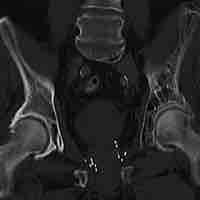

Diseases and Disorders of the Reproductive System

Thumbnail

Sexually Transmitted Diseases (STDs)

A sexually transmitted infection is passed between people during unprotected sexual intercourse with an infected partner.

Erectile Dysfunction and the Blue Pill

Erectile dysfunction (ED) is the inability to develop or maintain an erection during sexual intercourse.

Cervical Cancer

Cervical cancer is a cancer that originates in the cervix of a female.

Section 18

Pregnancy-Related Disorders

Ectopic Pregnancy

An ectopic pregnancy is implantation and development of the embryo outside the uterus, typically in the fallopian tubes.

Infertility

Infertility, in both males and females, refers to the inability to contribute to conception.